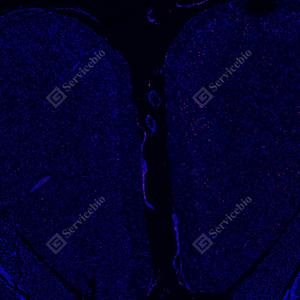

| IF检测c-Fos蛋白(货号 GB15069)(红色). 样品: 小鼠MACO模型脑组织, 4%多聚甲醛 (货号G1101) 固定12-24小时. 抗原修复: Tris-EDTA抗原修复液(pH 9.0) (G1203), 98℃, 20分钟. 封闭: 3% BSA(货号GC305010)的PBS溶液, 室温孵育30分钟. —抗: 1: 1000稀释, 4℃ 孵育过夜. 二抗: Cy3标记山羊抗兔IgG (H+L) (货号GB21303), 1: 300稀释, 室温孵育1小时. |